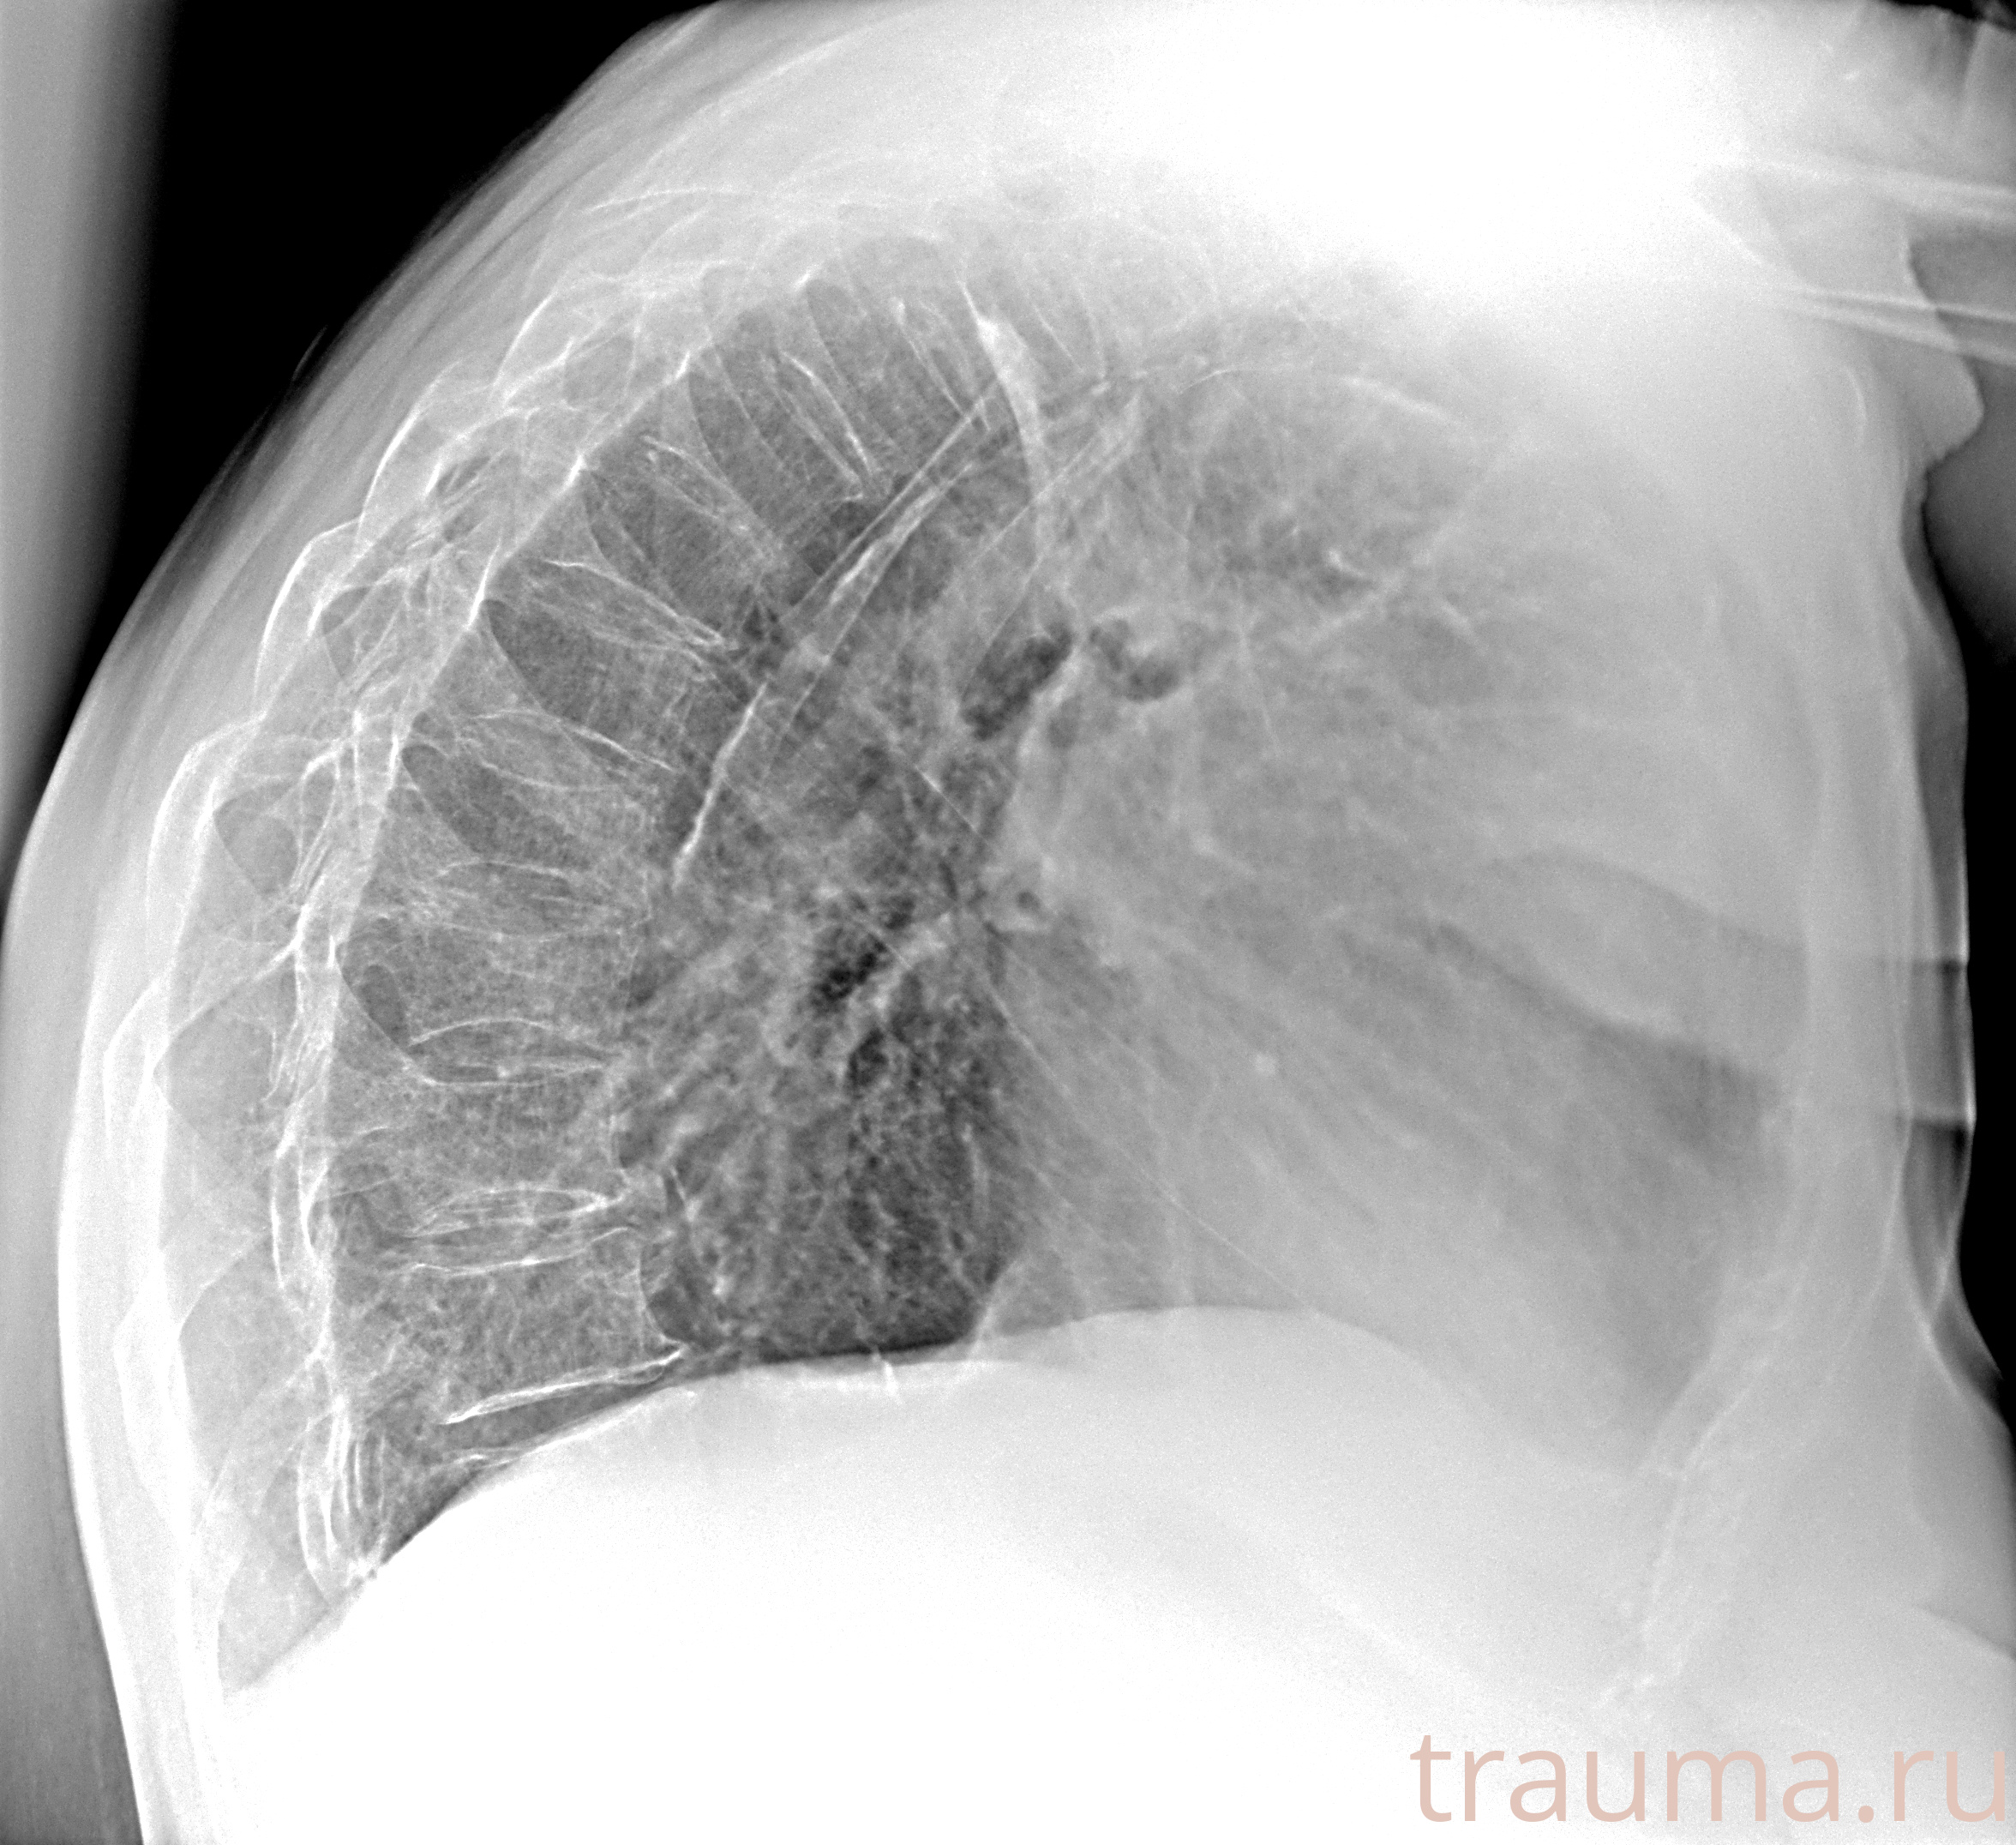

Рентгенограммы

Рентген на дому: по вашему адресу приезжает врач-рентгенолог, травматолог-ортопед с мобильным рентгеновским аппаратом, проводит диагностику травмы или заболевания, делает необходимые рентгенограммы, дает рекомендации по дальнейшему лечению. Получить качественные снимки в домашних условиях возможно благодаря уникальной методике, разработанной МосРентген Центром для института  Склифосовского

Яркость: 1   Контраст: 1   Инвертировать: 0 Увеличение: 1

Перетаскивайте мышь вверх/вниз для контраста, влево/право для яркости. Прокрутка колесом изменяет масштаб. Нажмите Сбросить для возврата к исходному изображению. При увеличении держите мышь в той области, которую хотите рассмотреть.